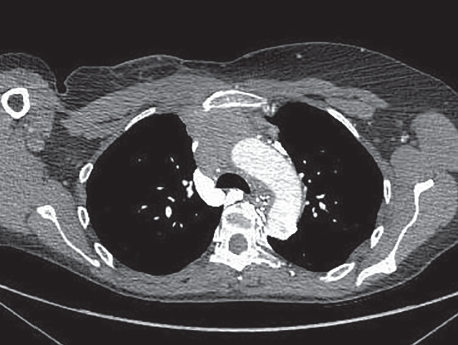

Breast cancer

11/19/2014

Vishesh Kumar, MD; Neeraj Saini, MD; Vivek Saini, MD

A 55-year-old female with history of triple negative breast cancer stage IIA status presents with pleuritic right-sided pain in the infrascapular region with progressive dyspnea on exertion over the past 2...